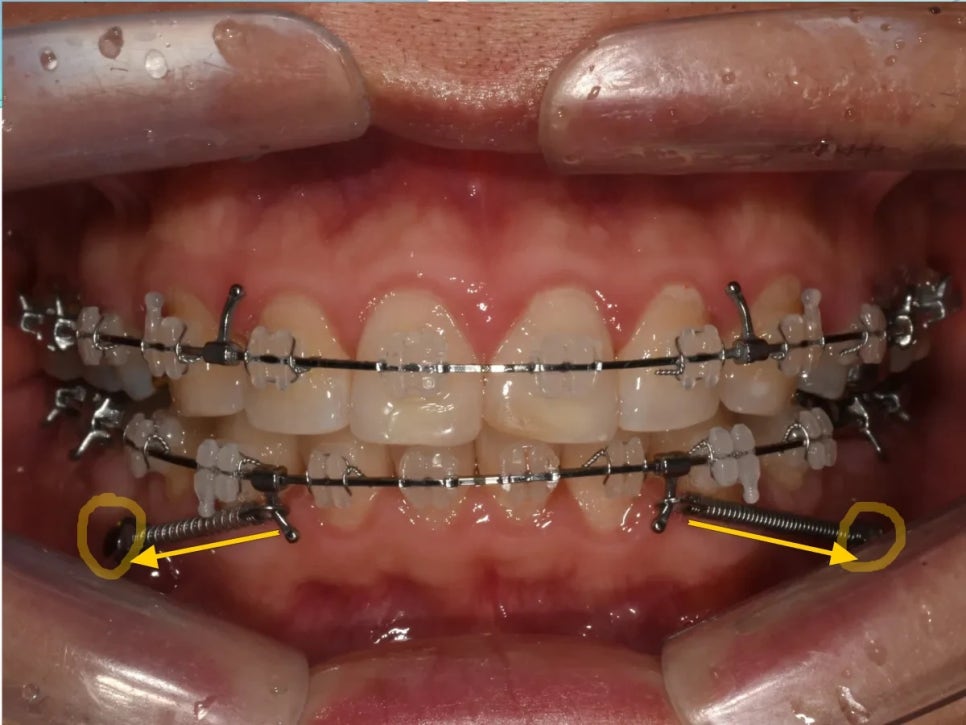

치료 과정 ② - 미니스크류를 이용한 전체 치열 후방이동

치아 배열과 과개교합 개선이 완료된 후, 드디어 본격적인 후방이동을 시작했습니다.

여기서 핵심 장치가 바로 미니스크류(TAD, Temporary Anchorage Device)입니다. 미니스크류는 뼈에 직접 심는 아주 작은 나사로, 치아를 당길 때 절대적인 고정점 역할을 합니다.

일반적인 교정에서는 치아끼리 서로 밀고 당기기 때문에 한쪽을 뒤로 보내면 반대쪽이 앞으로 나오는 한계가 있었습니다. 하지만 미니스크류는 뼈에 고정되어 있으므로 치열 전체를 한 방향(뒤쪽)으로 이동시키는 것이 가능합니다.

사랑니를 뺀 자리의 공간을 활용하여, 미니스크류에 연결된 탄성 체인으로 치열 전체를 조금씩 뒤로 이동시켰습니다.

미니스크류 식립 후 전체 치열 후방이동을 시작한 모습